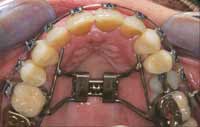

The orthopedic position established in Phase 1 was maintained in Phase 2 by constructing anterior composite incisal ramps/blocks for the lower anterior incisor occlusion. In the posterior, occlusal blocks were built on the occlusal surface of the second molars. This tripod (Figure 10) maintained the jaw and bite trajectory, which was established in Phase 1 through the NDA and the nighttime deprogrammer with palatal ramp. With this functional tripod established, the Phase 2 goals of orthopedic expansion could be accomplished as well as the orthodontic goals of rotating, leveling, and alignment. The upper-arch orthopedic development was accomplished through a fixed Hyrax expansion appliance (Figure 11 and Figure 12). The lower arch development was accomplished along with the upper arch and through use of straight wire techniques (Figure 13 and Figure 14). Final coupling of the dentition was accomplished through verticalization with eruption of the teeth through elastics. Phase 2 took 13 months. The patient then was placed in retention for an additional 6 months (Figure 15).

Figure 10 Tripod transfer established from Phase I orthotic after MMI was established.

Figure 11 Hyrax transverse expansion appliance with rectangular wire to establish proper torque.

Figure 12 Upper-arch clean up, orthopedic expansion, and orthodontics completed.

Figure 13 Note the rectangular wire used to create ideal torque.